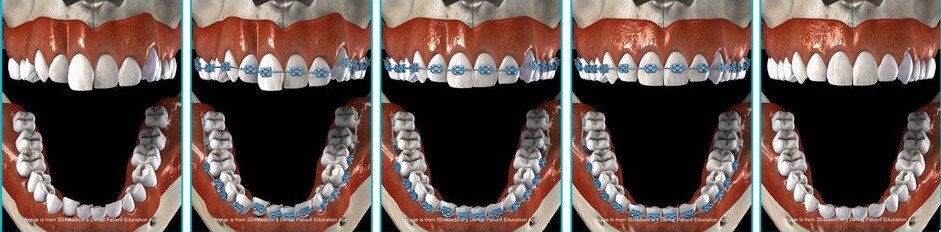

Ayrik Dis Tedavisinde Kullanilan Yontemler Ankara Dis Hekimi

Ayrik Dis Tedavisi Nedir Nasil Yapilir Dentvizyon

Ayrik Dis Tedavisinde Etkili Yontemler

Ayrik Disler Ve Tedavisi Dentaluna Group Agiz Ve Dis Sagligi Merkezi

Ayrik Disler Ve Tedavisi Dentaluna Group Agiz Ve Dis Sagligi Merkezi

Ayrik Dis Tedavisinde Kullanilan Yontemler Ankara Dis Hekimi

Ayrik Dis Tedavisi Ameliyat Com

Ayrik Dis Tedavisi Dis Araligi Kapatma

Ayrik Dis Tedavisinde Etkili Yontemler

Ayrik Disler Ve Tedavisi Dentaluna Group Agiz Ve Dis Sagligi Merkezi